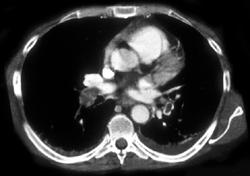

Jugular Vein Thrombosis